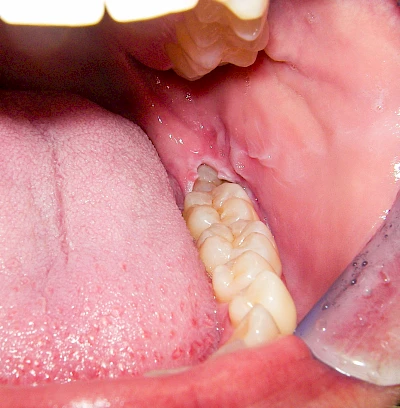

Diese Vermehrung von Bindegewebe in einem frei gewordenen Raum ist eine Sonderform der Anpassungsreaktion menschlicher Zellen und wird als Vakatwucherung bezeichnet.

Früher wurden im Unterkiefer mitunter Brücken zum Ersatz fehlender Zähne als sogenannte "Schwebebrücken" gestaltet. Die Idee dabei war, dass man die Brücke insgesamt besser reinigen kann. Allerdings war das für die Patienten mitunter irritierend für die Zunge und vor allem beim Essen gewöhnungsbedürftig. Teilweise haben sich hier reaktiv Vakatwucherungen der Kieferkammschleimhaut gebildet und den Raum unter der Brücke wieder verschlossen.